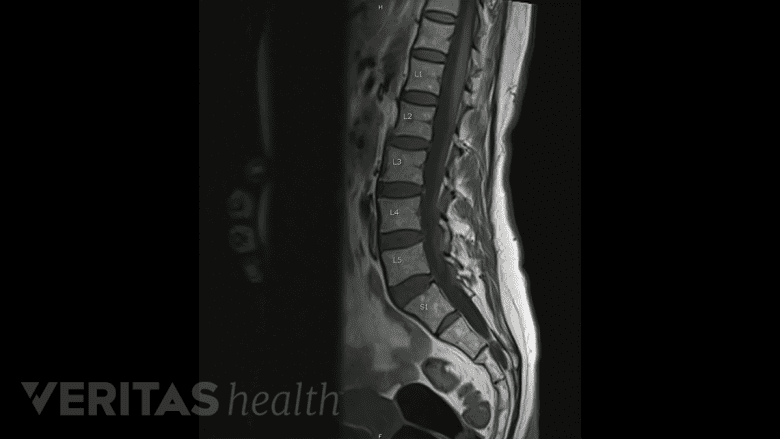

MRI scans help distinguish a chronic condition from an acute problem in certain situations.

Standard radiographs, magnetic resonance imaging (MRI), computed tomography (CT) scans, and other specialized tests may be used to check the facet joint and adjacent structures.

- MRI scans may be used for assessing the spine and its soft tissues, such as the discs and nerve roots. These scans may also help distinguish a chronic condition from an acute problem in certain situations. In analyzing a spine with a history of previous surgery, MRI’s are usually performed after a contrast dye is injected to better view blood flow in the region being studied.